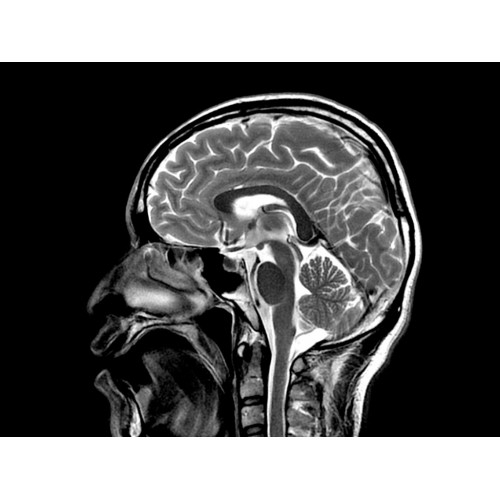

МР-томограф Optima MR450w позволяет получать изображения исключительно высокого качества, которые помогают установить диагноз. Чтобы удовлетворить ожидания клиентов в отношении высокого качества, в МР-томографе Optima MR450w были сохранены дополнительные возможности платформы Discoverу, привнесшие в его работу универсальность и мощь.

• Магнит переработанной конструкции — полностью новый магнит длиной 145 см обеспечивает однородную контрастность тканей в удобных для пациента условиях.

• Цифровой РЧ-приемник OpTix — эксклюзивная оптическая РЧ-система увеличивает четкость сигнала и его интенсивность, формируя чистые и резкие изображения.

• РЧ-катушки, оптимизированные для исследования конкретных участков тела — элементы катушек высокой плотности располагаются вокруг исследуемых участков тела и при необходимости обеспечивают расширенный охват и оптимальное качество изображений при каждой процедуре.